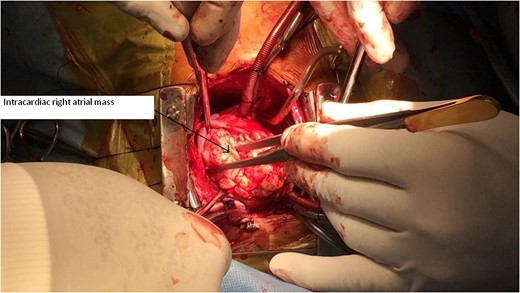

Primary cardiac tumour is a rare entity as secondaries in the heart are more common. A 2-year-old child was having repeated respiratory tract infection with poor oral intake and poor activity for 3 months. His symptoms progressed from New York Heart Association (NYHA) Class II to IV. On evaluation he had an intracardiac mass with extracardiac extension. Emergency tumour excision under deep hypothermic circulatory arrest was performed with provisional diagnosis of sarcoma. But Serum markers, histopathological examination and immunohistochemistry confirmed diagnosis of yolk sac tumour. Postoperative recovery was uneventful and the child was receiving adjuvant chemotherapy. Extensive literature review revealed only four cases of primary intracardiac yolk sac tumour published till date. Our case report is unique, in that intracardiac tumour had extracardiac extension by infiltration through right atrial wall. Previous four reports mention purely intracardiac mass.

A 2-year-old male child was brought to hospital with respiratory distress since last 2 weeks. He was having repeated respiratory tract infection since last 3 months along with poor oral intake and poor activity. His symptoms progressed from New York Heart Association (NYHA) Functional Class II to IV over last 2 weeks. On investigation at another hospital he was diagnosed with intracardiac mass having extracardiac extension. Parents brought the child to our hospital for further management.

CT Thorax showing intracardiac right atrial mass with extracardiac extension.

Primary cardiac tumour is rare. Only 25% of primary cardiac tumours are malignant. Survival rate for malignant primary cardiac tumours without surgical resection at 9–12 months is only 10%. Sarcomas constitute 75% of malignant primary cardiac tumour. Germ cell tumour is rare. Germ cell tumours are due to abnormal differentiation of foetal germ cells that arise from the foetal yolk sac. Normal migration of these germ cells may cause gonadal tumours, i.e. ovary and testis, whereas abnormal migration produces extragonadal tumours. Most cardiac germ cell tumours are teratomas. Yolk sac tumour is extremely rare. Surgical resection followed by chemotherapy is preferred treatment for yolk sac tumour. Only four cases of primary intracardiac yolk sac tumour are published till date in medical literature. Those are listed in Refs [2–5]. Three other cases of yolk sac tumour are reported but they were extracardiac being in pericardial cavity [6]. We are probably reporting fifth case of primary intracardiac yolk sac tumour.

Our case report is unique, in that intracardiac tumour had extracardiac extension by infiltration through right atrial wall. Previous four reports mention purely intracardiac mass. The rarity in the literature of such pathological occurrence makes our case report very unique.